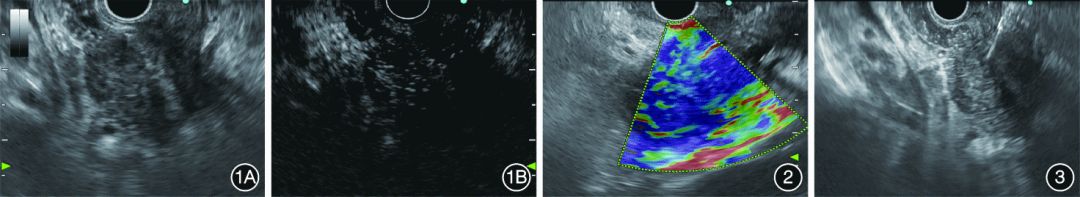

本中心共进行了9例肝脏转移灶CH⁃EUS⁃FNA(图1~图6)。选用25G(5例)、22G(5例)穿刺针,扇形穿刺,以生理盐水预充穿刺针道,连接10mL负压注射器或慢撤导丝,在没有ROSE的情况下,推荐穿刺肝脏病灶2×20次。

图1胰腺癌病灶行超声内镜造影1A:胰腺癌病灶在超声内镜下表现为低密度;1B:胰腺癌病灶在谐波造影增强超声内镜下表现为异质性、低增强图2胰腺癌病灶弹性成像显示病灶较硬图3胰腺癌病灶穿刺图4胰腺癌肝转移病灶行超声内镜造影4A:超声内镜下未见肝脏转移灶;4B:谐波造影增强超声内镜下见肝脏转移灶图5肝脏转移灶穿刺图6门静脉穿刺